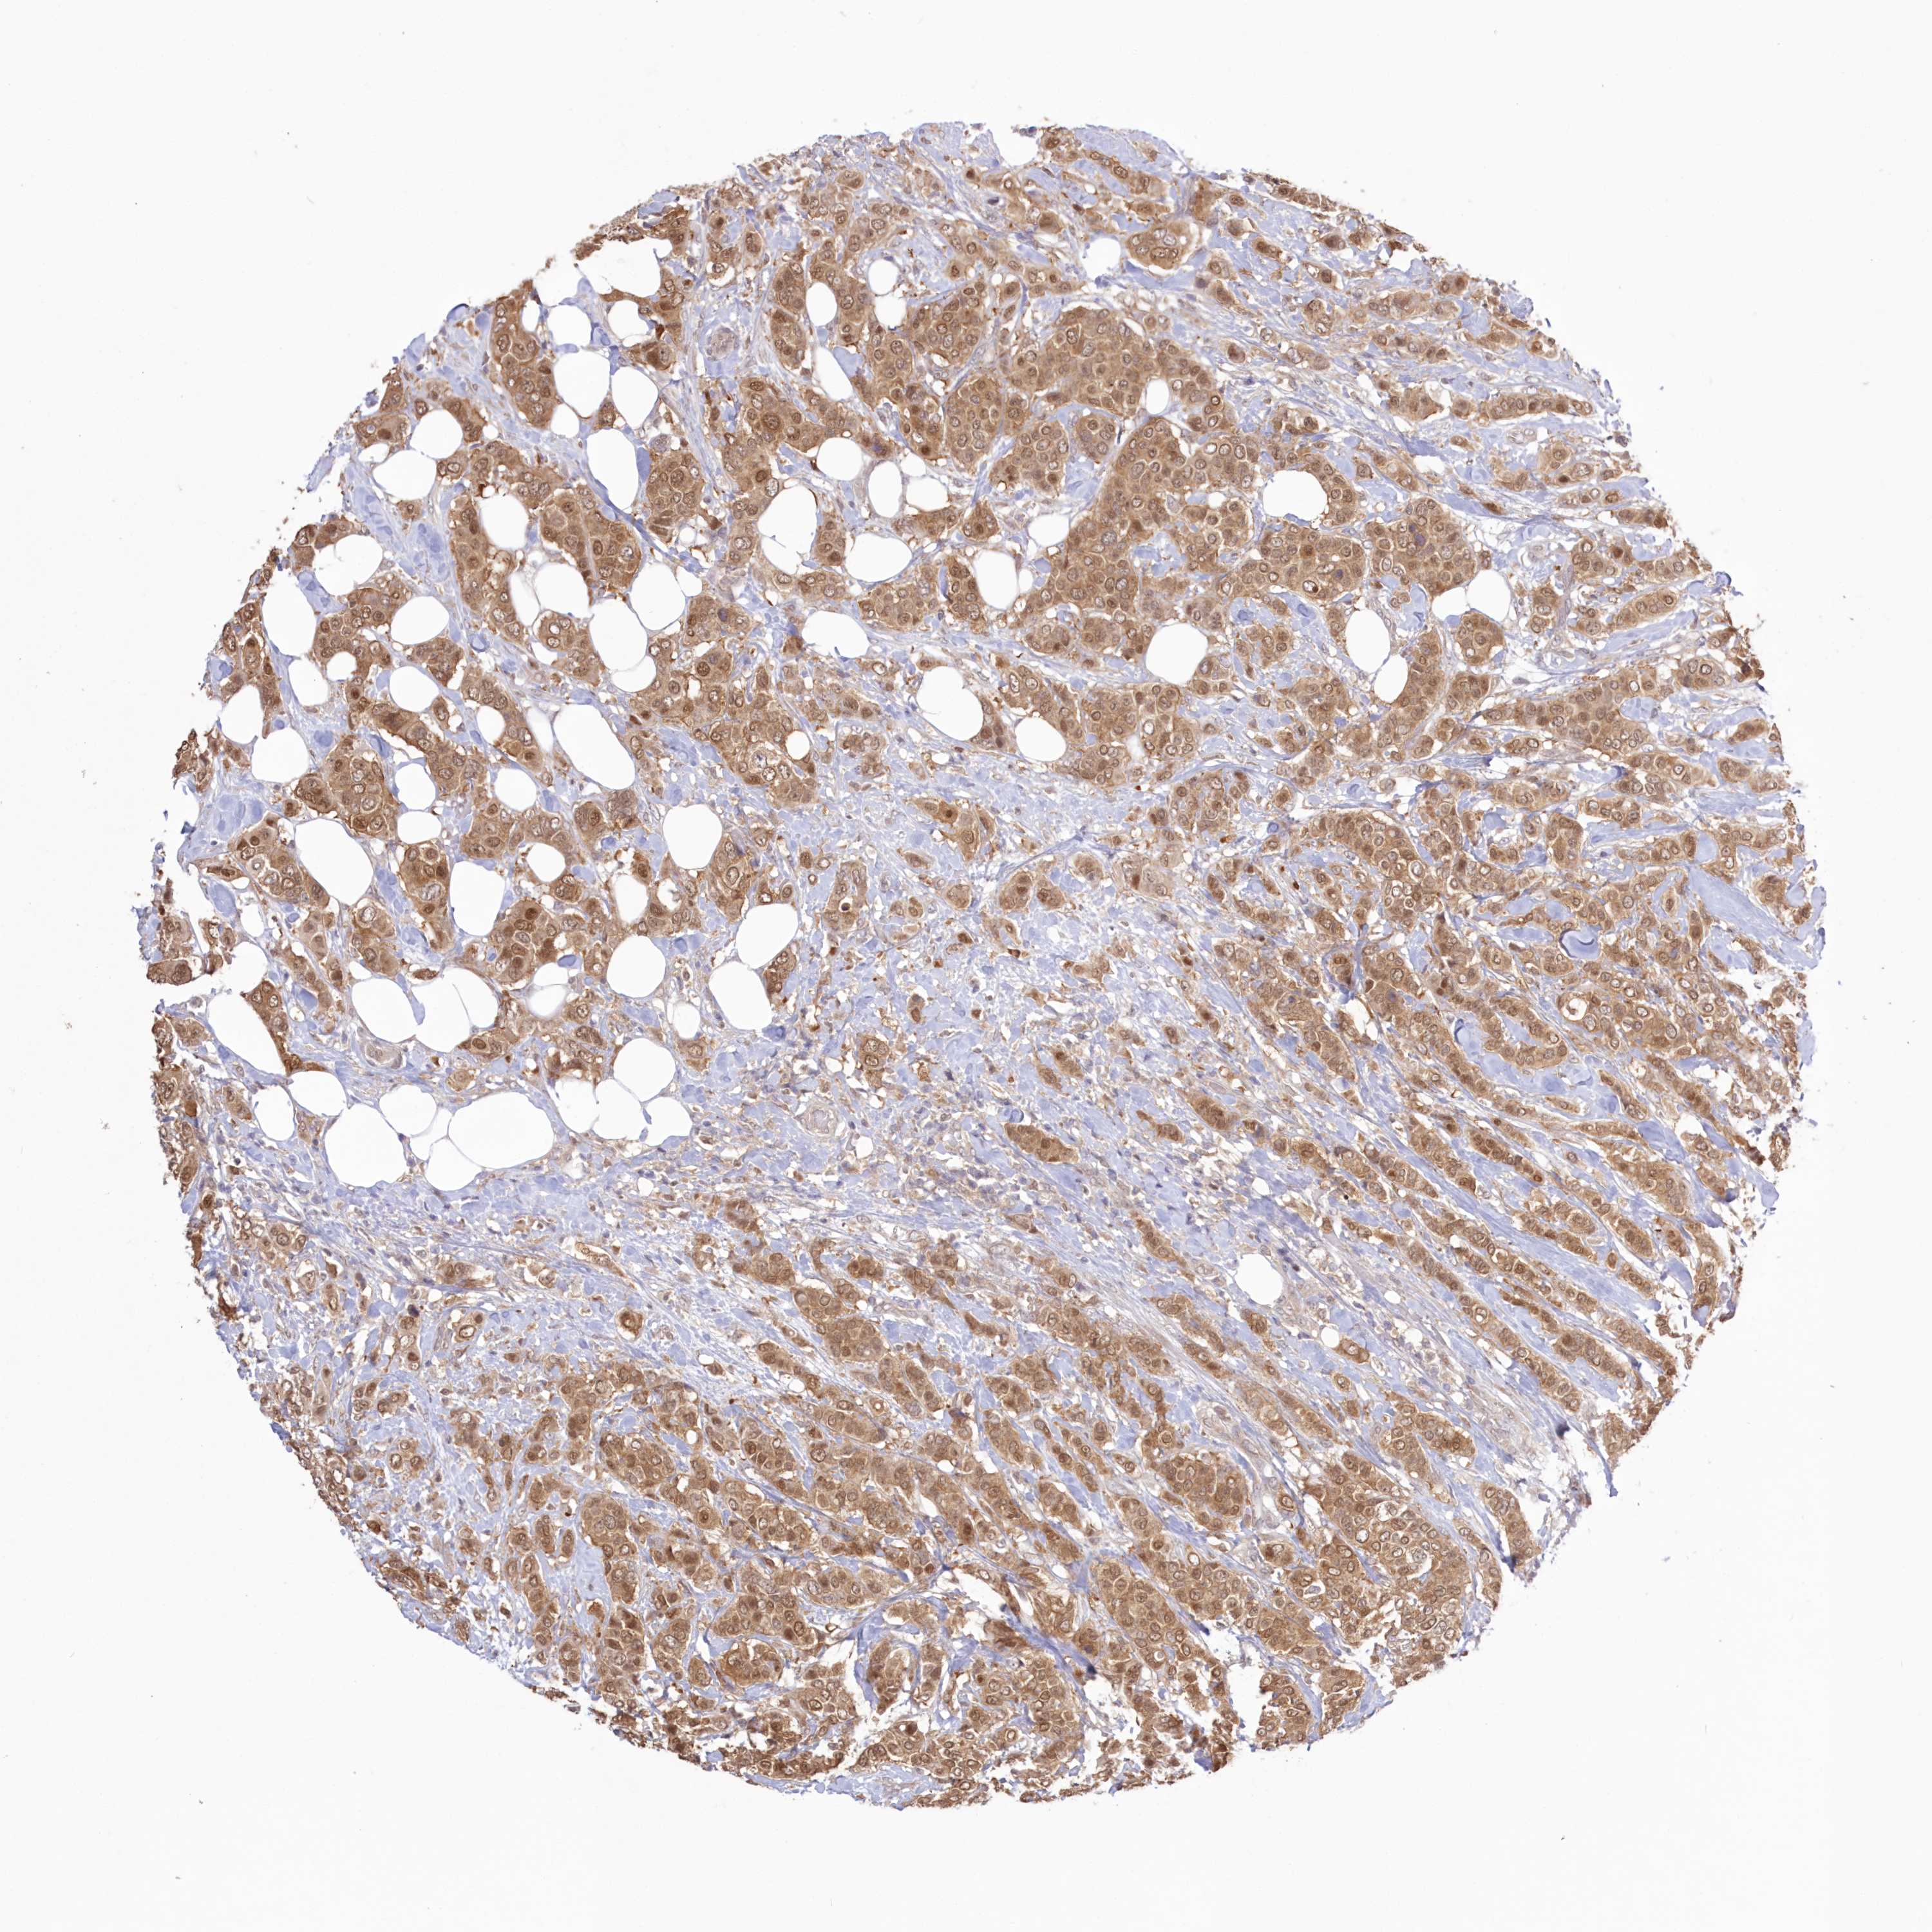

CANCER BREAST CANCER Show tissue menu

BRCA TCGA BRCA VALIDATION PROTEIN EXPRESSION